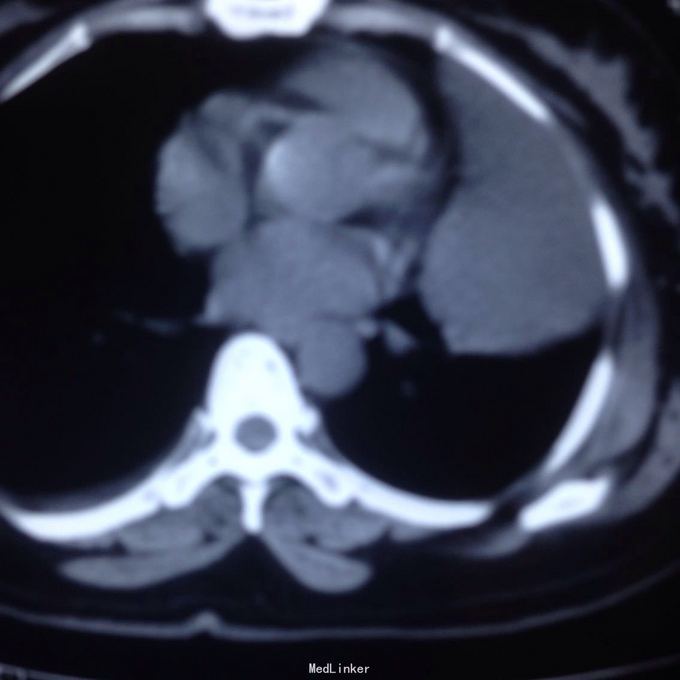

主诉:发现胸腔积液4月余。 现病史:患者4个月前因腰椎间盘突出在当地医院就诊,检查发现双侧少量胸腔积液,量不多,2个月后胸闷气短再次在当地医院复查胸部ct,提示双侧胸腔积液较前增多,左侧明显。

左侧胸腔包裹性积液? 完善胸腔b超提示左侧胸腔包裹性积液,最深处约59mm,内透声较差。予以定位后诊断性穿刺未抽出明显液体,当时考虑液体可能较粘稠或包裹分隔,遂决定予以小切口开胸探查。开胸后见胸腔积液,量约300ml,颜色较清亮,予以抽吸后在探查,见脏层及壁层胸膜无增厚及明显粘连,遂考虑不排除囊肿可能性,继续探查见胸膜顶靠近左纵隔处一囊壁,已破裂,囊壁挛缩成团,予以切除,术后病检为胸腺囊肿。

术后病检为胸腺囊肿。术后讨论:患者多次胸部ct均提示为包裹性积液,因囊肿较大,囊壁较薄,且靠近胸壁,易误诊为包裹性积液,但患者一直无发热病史,且复查ct积液位置靠胸前壁,术前应该考虑到囊肿可能,因患者经济较困难,至本院后未行增强ct,穿刺后考虑穿刺针将囊壁穿破,故开胸后未见完整囊肿,此类看似简单的病例容易由其他医院诊断误导,并且容易误诊。